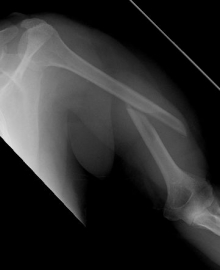

Picture: In the above pictures, a slightly shifted subcapital humeral fracture was internally splinted using intramedullary nail. The left picture is a follow-up examination half a year after the accident and shows the complete healing of the fracture with correct position of the bone.